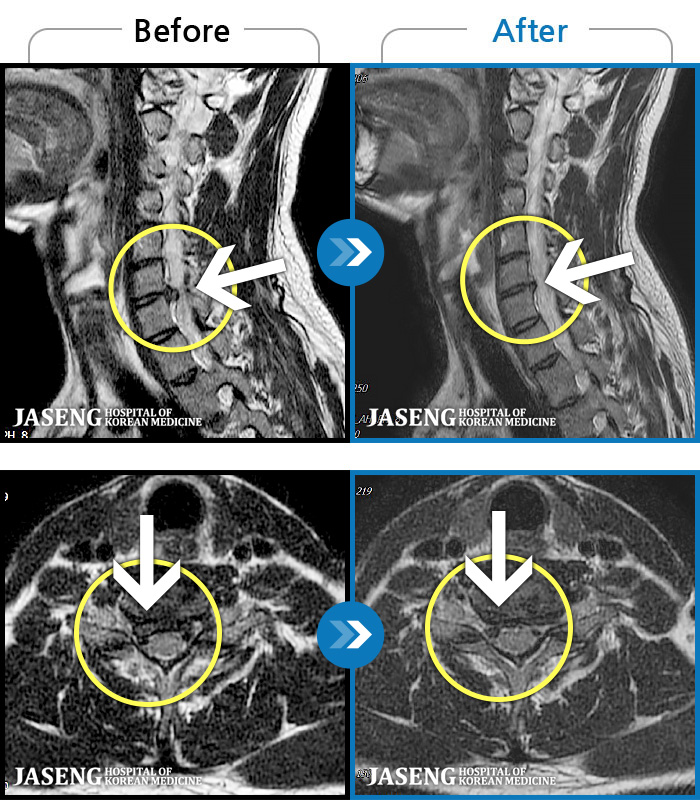

[뱸] 19.11.28~25.05.06